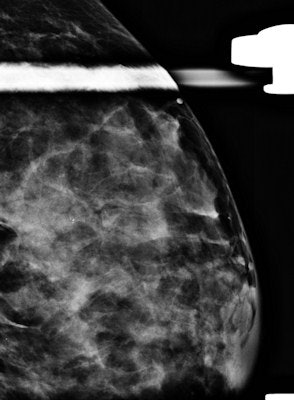

- Underlying dense breast tissues typically found in younger women can mask tumors, resulting in poor mammography performance.

The usefulness of mammography to diagnose breast cancer in young women is still debatable, Bullier and colleagues wrote. Abnormal findings were visible on 84 mammograms (86.6%); the 13 false negatives involved 10 breast parenchyma density BI-RADS 3 and three density BI-RADS 4. The rate of false negatives is relatively low given the majority of dense breast compositions on mammography in their series (73.2% density type 3 and 4).

The most common abnormality on mammography was masses with or without microcalcifications (53.5%). Also, the researchers could precisely describe all the imaging characteristics and found masses were usually irregular and spiculated.

"For isolated microcalcifications, mammography is the only satisfactory investigation, and we insist on a high level of suspicion in young women with breast lumps shown to have microcalcifications, with or without a mass or density, in the region of the clinical finding," they wrote. "Finally, only two mammograms were classified as BI-RADS ACR 3. Contrary to previous studies pointing out that conventional imaging in young women is less likely to be called suspicious or malignant, we found a majority of BI-RADS 4 and 5 images."